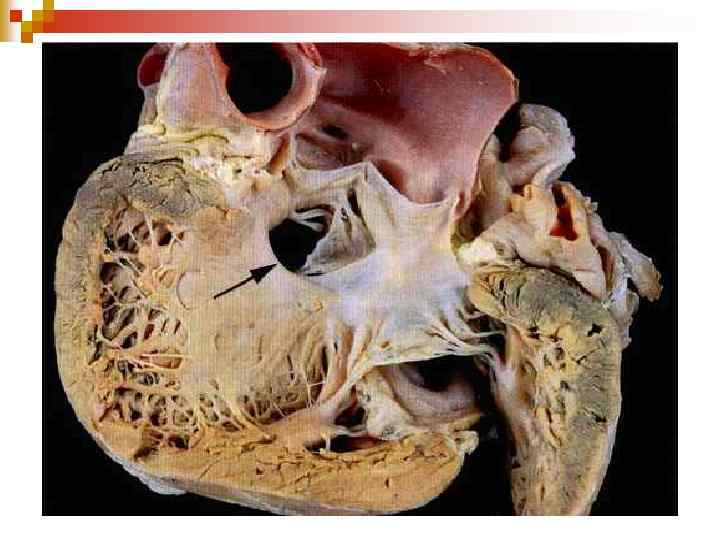

Аномалия Эбштейна является редким врожденным пороком сердца. Впервые описана в 1866 году патологоанатом Эбштейном. При этом пороке сердца створки правого атриовентрикулярного клапана исходят из стенок правого желудочка, а не из предсердно-желудочкового кольца и не полностью смыкаются (недостаточность трехстворчатого клапана). Таким образом, полость правого желудочка оказывается уменьшенной по сравнению с нормой, а часть правого желудочка от предсердно-желудочкового кольца (где клапан должен был находиться в норме) до смещенного вниз трехстворчатого клапана становится продолжением правого предсердия. Также при аномалии наблюдается незаращение овального отверстия (между правым и левым предсердиями). Из-за таких анатомических изменений аномалия Эбштейна характеризуется 1) недостаточностью трехстворчатого клапана (между правым предсердием и правым желудочком), 2) незаращённым овальным отверстием (между правым и левым предсердиями) и 3) уменьшением полости правого желудочка. Правое предсердие увеличивается в размерах и расширяется. Часть венозной крови перетекает в левое предсердие через открытое овальное отверстие и смешивается с артериальной. Это приводит к уменьшению содержания кислорода в артериальной крови и гипоксии органов и тканей. Возможны нарушения ритма сердца.